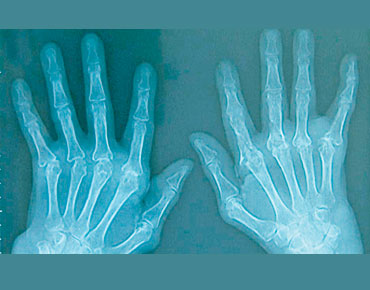

ويعود سبب هذا التصلب إلى إصابة مارتينا بالتهاب المفاصل الروماتويدي المزمن، وهو، كما تقول الدكتورة بريجيت كيتل، أحد أمراض المناعة الذاتية التي تؤدي إلى التهابات مختلفة في الجسم أهمها التهاب المفاصل، حيث يقوم جهاز المناعة ما يؤدي إلى التهابها .

ويعد العلاج بالعجين من أحد الطرق المستخدمة في العلاج الطبيعي أيضا، إذ يساعد مرضى الروماتيزم على تدريب المفاصل الصغيرة الحساسة في اليدين والقدمين، ما يجعل المفاصل أكثر قدرة على الحركة .